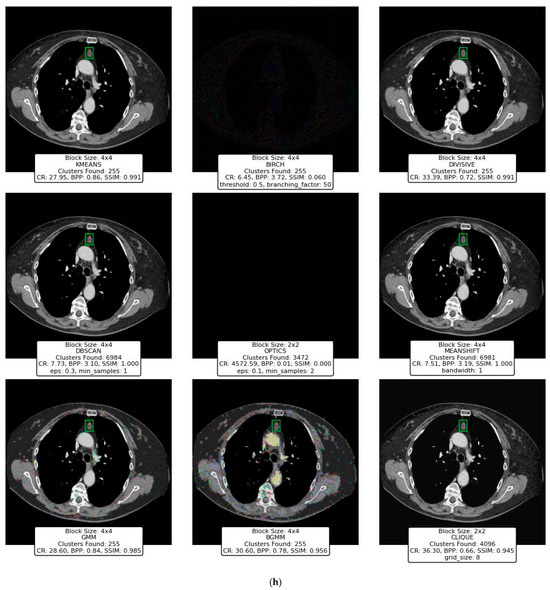

This section presents the performance evaluation of various clustering-based image compression techniques. Each method was applied to compress images using the proposed framework, followed by quantitative and qualitative assessments of the reconstructed images. Metrics such as CR, BPP, and SSIM were calculated to gauge the trade-offs between compression efficiency and image quality. Block sizes of 2 × 2, 4 × 4, 8 × 8, and 16 × 16 were applied across different clustering techniques to evaluate their impact on compression performance. However, some methods, such as BIRCH, DBSCAN, OPTICS, and CLIQUE, were only experimented with smaller block sizes (2 × 2, 4 × 4) due to the significant memory resources they require, which were not available on our hardware. The results highlight the strengths and limitations of each method, offering insights into their suitability for different compression scenarios. The findings are summarized and analyzed in the subsequent subsections.

The initial experimental results for image compression presented in this section utilized the widely recognized “Peppers” image (Figure 12) obtained from the Waterloo dataset [59], a benchmark resource for image processing research.

As the block size increases to 4 × 4, 8 × 8, and 16 × 16, a similar trend is observed where the number of clusters remains high, with minimal improvement in CR. The CR slightly increases from 1.48 (4 × 4) to 1.62 (16 × 16), but these values remain significantly lower compared to other clustering methods like K-Means or Divisive Clustering. This suggests that Mean Shift fails to provide effective compression because it tends to over-cluster image regions, leading to a high number of unique clusters that prevent substantial data reduction.

In conclusion, while Mean Shift preserves image quality perfectly (SSIM = 1.000), its compression efficiency is extremely poor. The high cluster count results in minimal data reduction, making it impractical for image compression. Unlike other methods that balance quality and compression, Mean Shift fails to achieve a desirable trade-off. Thus, it is not a viable option for practical image compression applications.

7.6. GMM and BGMM Clustering for Compression

Figure 19 and Figure 20 present the results of compressing an image using the GMM and BGMM clustering methods. For a block size of 2 × 2, both the GMM and BGMM achieve high compression ratios at lower cluster counts, with the GMM reaching a CR of 12.63 and BGMM at 12.07 with 31 clusters. As the cluster count increases to 255, the CR drops while SSIM improves, showing a trade-off between compression efficiency and quality. The highest SSIM values for both methods remain above 0.98, indicating strong image fidelity.

Figure 19.

Results of GMM clustering for compressing the Peppers image with varying numbers of clusters and block sizes.

Figure 20.

Results of BGMM clustering for compressing the Peppers image with varying numbers of clusters and block sizes.

With a 4 × 4 block size, compression ratios improve significantly, especially with lower cluster counts. Both methods reach CR values above 30 when using 31 clusters, while higher cluster counts lead to better SSIM at the cost of reduced compression efficiency. At 127 clusters, the GMM achieves a CR of 23.04 and an SSIM of 0.939, while the BGMM records 26.62 and 0.906, respectively.

At an 8 × 8 block size, compression ratios further increase, with the GMM reaching 86.50 and the BGMM 89.99 for 31 clusters. However, the SSIM remains relatively low in this setting. As clusters increase, SSIM improves, peaking at 0.987 for the GMM and 0.921 for BGMM at 255 clusters. This highlights that more clusters are necessary for maintaining image quality when using larger blocks.

For a 16 × 16 block size, maximum compression efficiency is achieved, with CR values exceeding 40 for low cluster counts. However, SSIM is initially lower due to larger data blocks capturing less detail. With 31 clusters, the GMM records a CR of 48.20 and SSIM of 0.952, while the BGMM achieves 49.16 and 0.950. At 255 clusters, both methods reach SSIM values above 0.96, providing high-quality reconstruction but at lower compression efficiency.

Overall, both the GMM and BGMM perform nearly identically, with the BGMM slightly favoring compression efficiency at lower cluster counts. The results confirm that distribution-based methods can maintain strong image fidelity while achieving significant compression, making them suitable for balancing storage efficiency and visual quality.

7.7. CLIQUE Clustering for Compression

Figure 21 presents the results of the CLIQUE clustering method applied for image compression with varying grid sizes, ranging from 1 to 8.5. The block size used in all experiments is fixed at 2 × 2, and the grid size controls the number of clusters and consequently affects compression performance and quality. Since CLIQUE is a grid-based clustering method, unclustered blocks are reassigned to the nearest dense grid cell, ensuring continuity in the compressed representation while minimizing data loss.

Figure 21.

Results of CLIQUE clustering for compressing the Peppers image with varying grid and block sizes.

For grid sizes 1.5 and 2.0, the algorithm identifies only 1 and 16 clusters, respectively. These settings result in poor visual quality, as evidenced by the low SSIM values (0.014 and 0.864, respectively) and the inability to retain structural details in the image. The CR values are exceptionally high (4572.59 and 59.10), but this comes at the cost of extreme data loss, as depicted by the highly distorted or gray images.

Increasing the grid size from 2.5 to 4.5 results in more clusters (81 to 256), which improves the image’s visual quality. The SSIM steadily increases, reaching 0.956 at a grid size of 4.5, indicating a good retention of structural similarity compared to the original image. Correspondingly, the CR values drop significantly (32.84 to 22.15), reflecting a more balanced trade-off between compression and quality. The images become visually more acceptable as the grid size increases, with better preservation of object edges and colors.

At grid sizes 5.0 to 6.0, the number of clusters increases drastically (625 and 1296), resulting in improved image quality. The SSIM values rise further (0.972 to 0.981), indicating near-perfect structural similarity. The BPP also increases moderately (1.38 to 1.65), demonstrating a slight trade-off in compression efficiency. The images exhibit finer details and color fidelity is well-preserved, making these grid sizes suitable for high-quality compression scenarios.

As the grid size increases from 6.5 to 8.5, the number of clusters grows exponentially (2401 to 4096). The SSIM approaches near-perfection (0.986 to 0.989), and the BPP increases significantly (1.92 to 2.04). These results reflect excellent image reconstruction quality with minimal perceptual differences from the original image. However, the CR values continue to decrease (12.53 to 11.74), highlighting the trade-off between compression efficiency and quality. These grid sizes are ideal for applications requiring minimal quality loss, even at the expense of reduced compression efficiency.

The performance of the CLIQUE method is highly dependent on the grid size, with a direct relationship between grid size and the number of clusters. Lower grid sizes result in fewer clusters, leading to higher compression ratios but significantly compromised image quality, as evidenced by low SSIM values and poor visual results. Medium grid sizes, such as 4.5 to 6.0, strike a balance between compression efficiency and image quality, maintaining good structural integrity while offering reasonable compression ratios. On the other hand, higher grid sizes (e.g., 6.5 to 8.5) generate more clusters, yielding near-perfect SSIM values and visually indistinguishable images from the original but at the cost of reduced compression efficiency.

7.8. Computational Efficiency Analysis

In this evaluation, all image compression techniques were applied using a fixed block size of 4 × 4 pixels. This uniform partitioning ensures consistency across different methods, allowing for a fair comparison of their computational efficiency. The experiments were conducted on a system with the following specifications:

- Processor: 11th Gen Intel® Core™ i7-11800H @ 2.30 GHz;

- Installed RAM: 32.0 GB;

- System Type: 64-bit operating system, x64-based processor;

- Operating System: Windows 11 Pro (Dev Version).

The results of Table 4 indicate significant variations in compression time among the techniques. CLIQUE exhibited the fastest performance, with the lowest processing time, making it the most efficient method in this study. K-Means followed with a relatively low computation time, reinforcing its suitability for real-time applications.

Table 4.

Compression and decompression time of different clustering methods.

Conversely, methods such as Mean Shift, GMM, and BGMM demonstrated considerably higher computational costs, likely due to their iterative nature and probabilistic modeling. OPTICS also showed a substantial runtime, reflecting its density-based approach’s complexity. Meanwhile, BIRCH, Divisive Clustering, and DBSCAN presented moderate execution times, balancing efficiency and effectiveness.

7.9. Discussion

The evaluation of the nine clustering techniques highlights the diverse strengths and limitations of each method in the context of image compression. Each technique offers unique trade-offs between compression efficiency, image quality, and computational complexity, making them suitable for different applications depending on the specific requirements.

K-Means stands out as a robust and versatile method for image compression, demonstrating a good balance between compression efficiency and image quality across various block sizes and cluster configurations. Its ability to produce consistent results with high SSIM values and moderate compression ratios makes it a strong candidate for applications requiring both visual fidelity and reasonable storage savings. However, its performance diminishes slightly with larger block sizes, where fine-grained image details are lost, leading to visible artifacts.

BIRCH, on the other hand, struggles to balance compression and quality, particularly with larger block sizes and higher thresholds. Its tendency to lose structural similarity at higher parameter settings indicates its limitations in preserving critical image features. While BIRCH may excel in other data clustering contexts, its application in image compression appears less effective compared to other techniques.

Divisive Clustering showcases excellent adaptability, particularly with smaller block sizes, where it maintains high SSIM values and reasonable compression ratios. As the block size increases, it achieves impressive compression efficiency with only a slight compromise in image quality. Its hierarchical nature enables it to provide granular control over the clustering process, making it well-suited for scenarios requiring a balance between compression and quality.

Density-based methods like DBSCAN and OPTICS highlight the challenges of applying these techniques to image compression. DBSCAN’s performance varies significantly with its parameters (eps and min_samples), often producing high SSIM values at the cost of computational overhead and impractical cluster counts. OPTICS, while theoretically advantageous for handling varying densities, shows limited effectiveness in this application, often leading to excessive compression at the expense of image structure. Both methods illustrate the importance of parameter tuning and the potential challenges of adapting density-based clustering for image compression.

Mean Shift emerges as a stable technique, particularly for smaller block sizes and lower bandwidth settings. Its non-parametric nature allows it to adapt well to the data, resulting in high SSIM values and low compression ratios. However, as block sizes increase, the sensitivity of Mean Shift to its bandwidth parameter diminishes, leading to less pronounced variations in results. This stability makes it an attractive option for applications where consistency across different settings is desirable.

The GMM and BGMM provide complementary perspectives on probabilistic clustering for image compression. The GMM demonstrates more pronounced changes in performance across block sizes and cluster counts, offering high compression ratios but at the cost of noticeable quality degradation for larger block sizes. In contrast, the BGMM delivers more consistent image quality with slightly higher BPP, making it a reliable choice for scenarios prioritizing visual fidelity over extreme compression efficiency.

Finally, CLIQUE, a grid-based clustering method, demonstrates the importance of balancing grid size with block size to achieve optimal results. While smaller grid sizes lead to significant compression, they often produce highly distorted images. Medium grid sizes strike a balance, maintaining reasonable compression ratios and good image quality, whereas larger grid sizes yield near-perfect SSIM values at the expense of reduced compression efficiency. CLIQUE’s grid-based approach offers a unique perspective, emphasizing the interplay between spatial granularity and compression performance.

In summary, the comparative analysis of these techniques underscores the necessity of selecting a clustering method tailored to the specific requirements of the application. Techniques like K-Means, Divisive Clustering, and BGMM excel in maintaining a balance between compression efficiency and image quality, making them suitable for general-purpose applications. Methods such as CLIQUE and Mean Shift provide specialized advantages, particularly when specific parameter configurations are carefully tuned. On the other hand, techniques like DBSCAN and OPTICS highlight the challenges of adapting density-based clustering to this domain, while BIRCH’s limitations in this context emphasize the importance of evaluating clustering methods in their intended use cases.

8. Validation of Compression Results Using CID22 Benchmark Dataset

The CID22 dataset [60] is a diverse collection of high-quality images specifically designed for evaluating image compression and other computer vision algorithms. It offers a wide range of visual content, including dynamic action scenes, intricate textures, vibrant colors, and varying levels of detail, making it an ideal choice for robust validation.

For this study, eight representative images were selected, as shown in Figure 22, covering diverse categories such as sports, mechanical objects, food, landscapes, macro photography, artwork, and medical images. This selection ensures comprehensive testing across different types of visual data, capturing various challenges like high-frequency details, smooth gradients, and complex patterns. The dataset’s diversity allows for a thorough assessment of the clustering-based compression techniques, providing insights into their performance across real-world scenarios.

Figure 22.

Benchmark images from the CID22 dataset.

Figure 23a–h and Table 5 show the results of compressing the benchmark images using the nine clustering techniques, in addition to PNG and JPEG compressors. Table 5 highlights the consistently high SSIM values observed at higher compression ratios, demonstrating the effectiveness of the compression method in preserving image quality while achieving significant data reduction.

Figure 23.

Results of clustering-based compression for different types of images. (a) Sports action (b). Mechanical objects (c). Vehicle (d). Food photography (e). Outdoor scenes with animals (f). Macro photography (g). Artwork. (h). Medical image.

Table 5.

CR and SSIM metrics for clustering-based compression, PNG and JPEG.

K-Means consistently delivers a balanced performance across all image categories. For instance, in sports and vehicles, it achieves high CR values (27.95 and 27.05, respectively) while maintaining excellent SSIM values (0.996 and 0.997). This indicates its effectiveness in preserving structural details while achieving reasonable compression. However, for more intricate scenes, such as macro photography, the CR increases to 30.58, suggesting its adaptability for detailed data. Overall, K-Means achieves a good balance between compression efficiency and image quality, making it versatile for a variety of image types.

BIRCH exhibits low performance in both CR and SSIM across all image types. For example, in food photography and macro photography, it achieves SSIM values of −0.004 and −0.032, respectively, with CR values of 1.67 and 3.39. These results indicate significant quality loss and inefficiency in compression. The method struggles to adapt to the complexities of natural scenes or high-detail photography. BIRCH’s weak performance suggests it may not be suitable for image compression tasks where quality retention is critical.

Divisive Clustering achieves high CR and SSIM values across most categories, particularly in medical and vehicles, with CR values of 33.39 and 28.34 and SSIM values of 0.991 and 0.994, respectively. These results show that the method preserves image quality effectively while achieving efficient compression. For macro photography, it performs similarly well, achieving an SSIM of 0.996. Divisive Clustering emerges as one of the top-performing techniques, maintaining a balance between efficiency and visual quality.

DBSCAN’s performance is highly dependent on parameter settings and image content. It achieves perfect SSIM values (1.0) for several categories, such as food photography and vehicles, but at the cost of extremely low CR values (e.g., 1.43 for artwork). This indicates over-segmentation, leading to inefficiencies in practical compression. In outdoor scenes and artwork, the method shows reduced CR values but still retains high SSIM, demonstrating its adaptability for specific types of data. However, its tendency to overfit or underperform depending on parameter tuning makes it less reliable overall.

OPTICS performs poorly in terms of compression efficiency and image quality. For most categories, such as sports and food photography, it achieves very high CR values (159.73 and 154.21) but with significantly degraded SSIM values (0.414 and 0.530). The images reconstructed using OPTICS often exhibit severe distortions and fail to retain meaningful structural details. The method’s performance suggests it is not well-suited for image compression tasks where preserving visual quality is important.

Mean Shift shows significant limitations in terms of compression efficiency. Despite achieving perfect SSIM values (1.0) across several categories (e.g., sports, food photography, and vehicles), its CR values are consistently low (e.g., 1.50 to 2.91). This indicates poor compression efficiency, making Mean Shift unsuitable for practical image compression tasks where achieving a high CR is essential. While it preserves image quality well, its limited efficiency renders it a less favorable choice for real-world applications.

The GMM achieves a strong balance between compression and quality, particularly in vehicles and sports, with CR values of 24.44 and 18.21 and SSIM values of 0.978 and 0.981, respectively. However, it struggles slightly with macro photography, where SSIM drops to 0.933. While the GMM performs well overall, its performance is slightly less consistent compared to Divisive Clustering or K-Means. Nonetheless, it remains a strong option for applications requiring good compression and quality balance.

The BGMM exhibits stable performance across all categories, retaining higher CR values than GMM in most cases. For instance, in vehicles and macro photography, the BGMM achieves CR values of 28.88 and 29.27, respectively. The SSIM values are also competitive, with a maximum of 0.968 in vehicles.

CLIQUE emerges as a good-performing method, combining high compression efficiency with excellent quality retention. In sports and vehicles, it achieves CR values of 14.03 and 14.40 and SSIM values of 0.992. In macro photography, it maintains a strong balance, achieving an SSIM of 0.963 while maintaining a reasonable CR of 29.29. CLIQUE adapts well to a wide range of image complexities and demonstrates consistent performance, making it a strong competitor to K-Means and Divisive Clustering.

PNG consistently achieves low CR across all image categories, reinforcing its lossless nature. The CR values for PNG range from 1.38 for outdoor scenes to 4.80 for medical images, confirming that PNG prioritizes image quality preservation over compression efficiency.

JPEG provides significantly better compression than PNG, with a CR of 38.40 for macro photography, making it the most effective method in that category. It also performs well for sports action and outdoor scenes, both at 24.00, and for food photography at 21.33. However, JPEG does not always surpass clustering-based techniques, particularly for medical images, where it has a CR of 24.00 compared to CLIQUE’s 36.30.

In summary, K-Means, Divisive Clustering, and CLIQUE stand out as the most reliable clustering methods for image compression, offering consistent performance across diverse image types. These methods effectively balance compression efficiency (high CR) and image quality (high SSIM), making them suitable for a wide range of applications. GMM and BGMM also provide good results but may require careful parameter tuning to achieve optimal performance. Mean Shift, despite its ability to retain image quality, is limited by poor compression efficiency, making it unsuitable for most compression scenarios. BIRCH, DBSCAN, and OPTICS exhibit significant limitations in either quality retention or compression efficiency, rendering them less favorable for practical applications.

9. Conclusions and Future Research Directions

Image compression is a crucial aspect of digital media management, enabling efficient storage, transmission, and accessibility of large-scale image data. With the growing demand for high-quality visual content in applications ranging from healthcare to entertainment, the development of effective compression methods is more important than ever. Clustering techniques offer a promising approach to image compression by grouping pixel data based on similarity, allowing for reduced storage requirements while maintaining structural fidelity. In this paper, we systematically evaluated nine clustering techniques—K-Means, BIRCH, Divisive Clustering, DBSCAN, OPTICS, Mean Shift, GMM, BGMM, and CLIQUE—for their performance in compressing images.

The findings highlight the versatility and efficacy of clustering-based approaches, with K-Means, Divisive Clustering, and CLIQUE emerging as the most reliable methods. K-Means demonstrated exceptional adaptability, balancing compression efficiency and image quality, making it a go-to technique for various image types and complexities. Divisive Clustering, with its hierarchical methodology, proved adept at preserving structural integrity while achieving substantial compression, particularly for larger block sizes. CLIQUE, leveraging its grid-based strategy, offered a unique combination of high CR and SSIM values, placing it as a strong contender alongside K-Means and Divisive Clustering. While the GMM and BGMM were effective in retaining structural details, their compression efficiency was slightly lower than the top-performing techniques. Mean Shift preserved image quality but suffered from low CR, limiting its practicality. Techniques like BIRCH, DBSCAN, and OPTICS struggled to balance compression and quality, often yielding distorted images or suboptimal CR values.

Building on the findings of this paper, future research can explore several avenues to further enhance clustering-based image compression. One promising direction is the integration of clustering techniques with Discrete Cosine Transform (DCT) in JPEG compression, which presents a promising hybrid approach that leverages the strengths of both methods. Traditional JPEG compression relies on DCT to convert image blocks from the spatial domain to the frequency domain, where high-frequency coefficients can be quantized and discarded to achieve compression. However, this process does not exploit the inherent redundancy in image content effectively. By introducing clustering as a preprocessing step, image blocks with similar patterns can be grouped together before applying DCT, leading to more efficient coefficient encoding and improved compression ratios. Furthermore, combining clustering with adaptive quantization and entropy coding in JPEG could further optimize compression, particularly for complex images with varying textures.

Author Contributions

Conceptualization, M.O.; methodology, M.O. and M.K. software, M.O.; validation, M.O. and M.K.; formal analysis, M.O.; investigation, M.O. and M.K.; resources, K.S. and A.A.; data curation, M.O. and M.K.; writing—original draft preparation, M.O.; writing—review and editing, M.K., K.S. and A.A.; visualization, M.O.; supervision, M.O.; project administration, M.O.; funding acquisition, M.O., K.S. and A.A. All authors have read and agreed to the published version of the manuscript.

Funding

This research was funded by The American University of Ras Al Khaimah, grant number ENGR/001/25.

Institutional Review Board Statement

Not applicable.

Data Availability Statement

Data will be available upon request.

Acknowledgments

The authors would like to express their gratitude to ChatGPT-4-turbo by OpenAI for its invaluable assistance in the preparation of this paper. Its support in drafting, refining, and structuring the content has significantly contributed to the clarity and quality of this work.

Conflicts of Interest

The authors declare no conflicts of interest.

Abbreviations

The following abbreviations are used in this manuscript:

| BGMM | Bayesian Gaussian Mixture Model |

| BIRCH | Balanced Iterative Reducing and Clustering using Hierarchies |

| BPP | Bits Per Pixel |

| CF | Clustering Feature |

| CLIQUE | Clustering In Quest |

| CR | Compression Ratio |

| DBSCAN | Density-Based Spatial Clustering of Applications with Noise |

| Eps | Epsilon |

| GMM | Gaussian Mixture Model |

| Min_Pts | Minimum Points |

| OPTICS | Ordering Points to Identify the Clustering Structure |

| PSNR | Peak signal-to-noise ratio |

| SSIM | Structural Similarity Index |

References

- Kou, W. Digital Image Compression: Algorithms and Standards; Springer Science & Business Media: Berlin, Germany, 2013; Volume 333, pp. 1–15. [Google Scholar]

- Vincze, M.; Molnar, B.; Kozlovszky, M. Real-Time Network Video Data Streaming in Digital Medicine. Computers 2023, 12, 234. [Google Scholar] [CrossRef]

- Mochurad, L. A Comparison of Machine Learning-Based and Conventional Technologies for Video Compression. Technologies 2024, 12, 52. [Google Scholar] [CrossRef]

- Auli-Llinas, F. Fast and Efficient Entropy Coding Architectures for Massive Data Compression. Technologies 2023, 11, 132. [Google Scholar] [CrossRef]

- Frackiewicz, M.; Mandrella, A.; Palus, H. Fast color quantization by K-means clustering combined with image sampling. Symmetry 2019, 11, 963. [Google Scholar] [CrossRef]

- Báscones, D.; González, C.; Mozos, D. Hyperspectral image compression using vector quantization, PCA and JPEG2000. Remote Sens. 2018, 10, 907. [Google Scholar] [CrossRef]

- Guerra, R.; Barrios, Y.; Díaz, M.; Santos, L.; López, S.; Sarmiento, R. A new algorithm for the on-board compression of hyperspectral images. Remote Sens. 2018, 10, 428. [Google Scholar] [CrossRef]

- Ungureanu, V.-I.; Negirla, P.; Korodi, A. Image-Compression Techniques: Classical and “Region-of-Interest-Based” Approaches Presented in Recent Papers. Sensors 2024, 24, 791. [Google Scholar] [CrossRef]

- Uthayakumar, J.; Elhoseny, M.; Shankar, K. Highly reliable and low-complexity image compression scheme using neighborhood correlation sequence algorithm in WSN. IEEE Trans. Reliab. 2020, 69, 1398–1423. [Google Scholar] [CrossRef]

- Khalaf, W.; Zaghar, D.; Hashim, N. Enhancement of curve-fitting image compression using hyperbolic function. Symmetry 2019, 11, 291. [Google Scholar] [CrossRef]

- Fernandes, V.; Carvalho, G.; Pereira, V.; Bernardino, J. Analyzing Data Reduction Techniques: An Experimental Perspective. Appl. Sci. 2024, 14, 3436. [Google Scholar] [CrossRef]

- Hoeltgen, L.; Peter, P.; Breuß, M. Clustering-based quantisation for PDE-based image compression. Signal Image Video Process. 2018, 12, 411–419. [Google Scholar] [CrossRef]

- Mulla, A.; Gunjikar, N.; Naik, R. Comparison of Different Image Compression Techniques. Int. J. Comput. Appl. 2013, 70, 7–12. [Google Scholar] [CrossRef]

- Baid, U.; Talbar, S. Comparative study of k-means, gaussian mixture model, fuzzy c-means algorithms for brain tumor segmentation. In Proceedings of the International Conference on Communication and Signal Processing 2016 (ICCASP 2016), Lonere, India, 26–27 December 2016; Atlantis Press: Dordrecht, The Netherlands, 2016; pp. 583–588. [Google Scholar]

- Fradkin, D.; Muchnik, I.B.; Streltsov, S. Image compression in real-time multiprocessor systems using divisive k-means clustering. In Proceedings of the IEMC’03 Proceedings. Managing Technologically Driven Organizations: The Human Side of Innovation and Change (IEEE Cat. No. 03CH37502), Cambridge, MA, USA, 30 September–4 October 2003; IEEE: Piscataway, NJ, USA, 2003; pp. 506–511. [Google Scholar]

- Jaseela, C.C.; James, A. A new approach to fractal image compression using DBSCAN. Int. J. Electr. Energy 2014, 2, 18–22. [Google Scholar] [CrossRef]

- Fu, H.; Liang, F.; Lin, J.; Li, B.; Akbari, M.; Liang, J.; Zhang, G.; Liu, D.; Tu, C.; Han, J. Learned image compression with gaussian-laplacian-logistic mixture model and concatenated residual modules. IEEE Trans. Image Process. 2023, 32, 2063–2076. [Google Scholar] [CrossRef] [PubMed]

- Gersho, A.; Gray, R.M. Vector Quantization and Signal Compression; Springer Science & Business Media: Berlin, Germany, 2012; Volume 159. [Google Scholar]

- Linde, Y.; Buzo, A.; Gray, R. An algorithm for vector quantizer design. IEEE Trans. Commun. 2003, 28, 84–95. [Google Scholar] [CrossRef]

- Jayant, N.S.; Noll, P. Digital Coding of Waveforms: Principles and Applications to Speech and Video; Prentice-Hall: Englewood Cliffs, NJ, USA, 1984; Volume 2. [Google Scholar]

- Mbuga, F.; Tortora, C. Spectral clustering of mixed-type data. Stats 2021, 5, 1–11. [Google Scholar] [CrossRef]

- Nies, H.W.; Zakaria, Z.; Mohamad, M.S.; Chan, W.H.; Zaki, N.; Sinnott, R.O.; Napis, S.; Chamoso, P.; Omatu, S.; Corchado, J.M. A review of computational methods for clustering genes with similar biological functions. Processes 2019, 7, 550. [Google Scholar] [CrossRef]